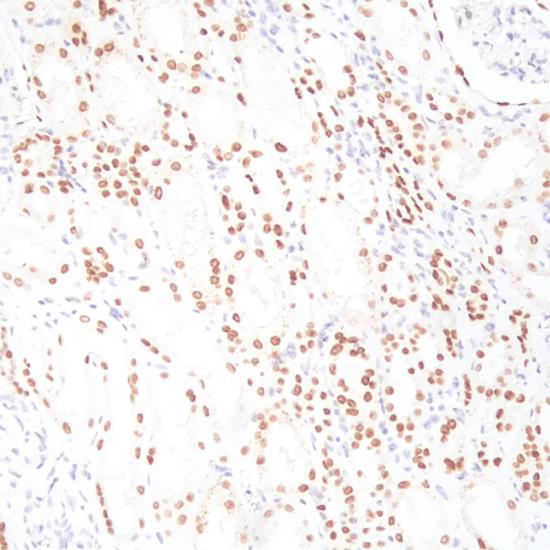

HNF1-Beta

HNF1-Beta抗體試劑(免疫組織化學(xué)) 閩廈械備20180228號(hào)

• 陽(yáng)性部位:

細(xì)胞核

• 陽(yáng)性對(duì)照:

腎透明細(xì)胞癌

HNF1-Beta是一種與多種器官,特別是肝、腎、胰腺和苗勒管胚胎發(fā)育相關(guān)的轉(zhuǎn)錄因子。在診斷卵巢透明細(xì)胞癌中, HNF1-Beta是一種比較敏感且特異的標(biāo)志物,尤其是區(qū)分伴有透明細(xì)胞改變的卵巢漿液性癌和子宮內(nèi)膜樣癌。